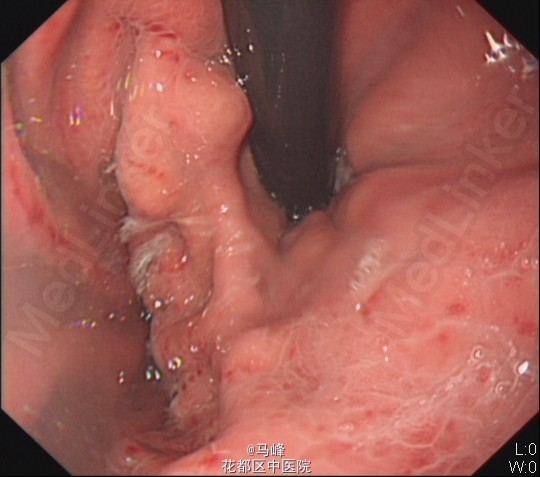

老年男性,主诉:发现乙肝肝硬化7月,返院复查。既往有乙型肝炎病史,目前已服用“博路定 0.5mg qn”抗病毒治疗4月。 现病史:患者7月前外院诊断“乙肝肝硬化”。后为求进一步诊治,来我科住院治疗,分别于2014-9-9、2014-10-21及2015-3-20在我院行胃镜下“食管重度静脉曲张套扎术”治疗,术后无诉不适,好转出院。

入院后予抗病毒、补充营养等对症支持治疗,排除禁忌症后于13/5在无痛胃镜下行食管重度静脉曲张套扎术,术后予加强护胃治疗。